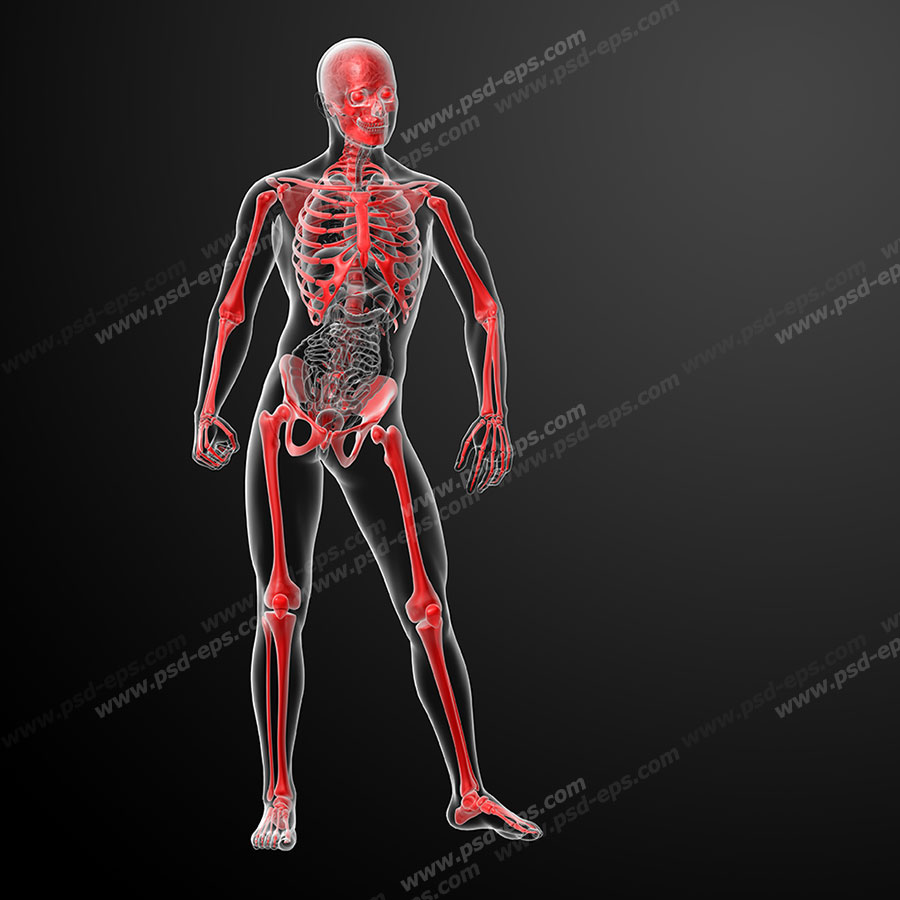

عکس اسکلت بدن انسان

آناتومی سه بعدی بدن انسان عکس گرافی بدن.

عکس اسکلت بدن انسان. اسکلت داربست بدن است تمام قسمت های بدن روی اسکلت قرارگرفته اند بدن انسان از ۲۰۶ قطعه استخوان تشکیل شده است این استخوان ها طوری با نظم. هر قسمت بدن از انواع مختلف سلول تشکیل شده است. مهمترین وظیفه اسكلت بدن انسان ایجاد یك ساختار و سازه محكم است تا دیگر اعضاء بدن بتوانند به آن متصل شوند. سازه و چهارچوب اصلی بدن.

اسکلت داربست بدن است تمام قسمت های بدن روی اسکلت قرارگرفته اند بدن انسان از ۲۰۶ قطعه استخوان تشکیل شده است این استخوان ها طوری با نظم کنار هم قرار گرفته اند که انسان را قادر می سازد حرکات دقیقی داشته باشد. بدون اسكلت بدن مانند كرم شل و نرم است و این نوع شكل بندی نمیتواند. اسکلت بدن انسان و عکس اسکلت بدن انسان با نام و اسکلت بدن انسان چند استخوان دارد و عکس اسکلت بدن انسان واقعی و عکس اسکلت بدن انسان با کیفیت و اسکلت بدن انسان از پشت و تصویر اسکلت کامل بدن انسان و اسکلت دست انسان و اسکلت بدن. معرفی بدن انسان اسکلیت.

اسکلت داربست بدن است تمام قسمت های بدن روی اسکلت قرارگرفته اند بدن انسان از ۲۰۶ قطعه استخوان تشکیل شده است این استخوان ها طوری با نظم کنار هم قرار گرفته اند که انسان را قادر می سازد حرکات دقیقی داشته باشد. استخوان یک نسج بسیار محکم است زیرا در ترکیب آن منرالها مانند کلسیم و دیگر وجود. اسکلت داربست بدن است تمام قسمت های بدن روی اسکلت قرارگرفته اند بدن انسان از ۲۰۶ قطعه استخوان تشکیل شده است این استخوان ها طوری با نظم کنار هم قرار گرفته اند که انسان را قادر می سازد حرکات دقیقی داشته باشد. آناتومی سه بعدی بدن انسان عکس گرافی بدن امعاء و احشاء بدن آناتومی سه بعدی بدن انسان عکس گرافی بدن امعاء و احشاء بدن قلب کبد روده.

اسکلت داربست بدن است تمام قسمت های بدن روی اسکلت قرارگرفته اند بدن انسان از 206 قطعه استخوان تشکیل شده است این استخوان ها طوری با نظم کنار هم قرار گرفته اند که انسان را قادر می سازد حرکات دقیقی داشته باشد. اسكلت به بدن شكل میدهد. عکس اسکلت بدن انسان زن و مرد آناتومی ساتین 16 سپتامبر 2017.